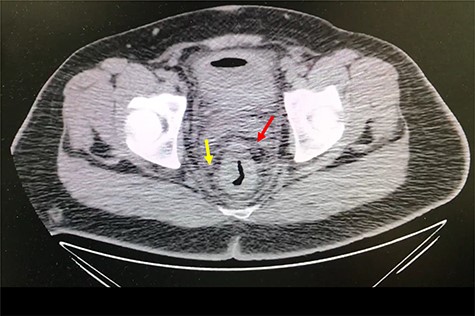

A 32-year-old man with no past medical or surgical history presented to the emergency department (ED) in April 2018, distressed and complaining of worsening pneumaturia for the past 3 days. The patient reported a 2-week history of polyuria, dysuria, suprapubic pain, tenesmus and inability to control his sphincters, prior to the ED-onset presentation. Further history revealed a 50-pound involuntary weight loss in a 5-month period, with partially treated urinary tract infections without resolution. He denied toxic habits, high-risk sexual behavior nor family history for colorectal cancer or inflammatory bowel disease. Based on the symptoms described, the rare triad of Gouverneur’s syndrome related to the EVF was considered. Physical evaluation revealed no palpable anorectal masses, adequate rectal tone and no visible gross blood. Urine analysis showed pyuria, hematuria, proteinuria with urine culture positive for Escherichia coli. Abdominopelvic computed tomography (CT) scan showed circumferential wall thickening of the rectum with surrounding fat stranding and numerous prominent pelvic lymph nodes (Fig. 1). Additionally, the scan showed pericolonic gas and fluid collection with a fistulous tract adjacent to the proximal rectum and the bladder (Fig. 2). In Figure 3, two hepatic hypodense lesions located in the right lobe of the liver were identified suggestive of metastasis. During colonoscopy, at approximately 20 cm from the anal verge a large, firm, irregular, friable, concentric mass was identified obstructing 95% of the lumen (Fig. 4). During surgery, the mass was not amenable for resection, due to its low pelvic location and size; a loop colostomy was performed for decompression, with liver tru-cut needle biopsy. Intraoperative cystoscopy was unsuccessful in placement of ureteral stents due to tumor invasion to the bladder.

Axial abdomen and pelvis CT scan showing enlarged lymph nodes (yellow arrow) and fat standing around rectum (red arrow).